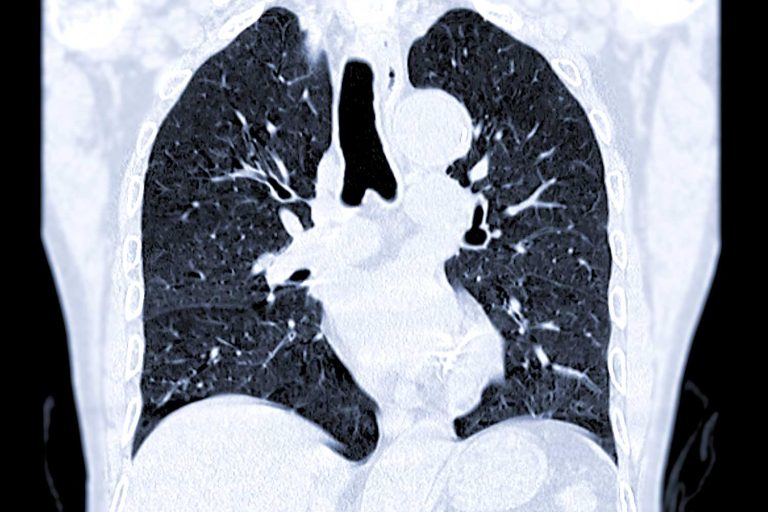

Computed Tomography (CT) is a non-invasive imaging technique that combines X-rays and computer technology to produce detailed cross-sectional images of the body. CT scans offer far more detail than traditional X-rays, making them essential for diagnosing a wide range of conditions. CT scans are quick, painless, and often completed in less than 15 minutes.

High-Resolution Imaging with Siemens Somatom Definition AS

At IPMC, we’re proud to offer the Siemens Somatom Definition AS 64-slice CT scanner—a powerful, high-resolution system designed for speed, comfort, and precision. This advanced CT scanner delivers:

- Comprehensive diagnostics from head to toe

- Ideal for cardiovascular, neurological, orthopedic, and full-body imaging

This technology allows us to capture highly detailed images in seconds while keeping your experience comfortable and efficient.